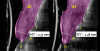

Fig 1. Clinical view at presentation.

Figure 1

Fig 19. Ultrasonographic comparison of the volumetric gain obtained with the intervention. Fig 19: Baseline. Fig 20: 1-year post-treatment. “C” identifies the crown, “A” the abutment, “I” the implant fixture, and “ST” the soft tissue. The soft tissue at baseline (Fig 19) is highlighted in blue, while the soft tissue at the 1-year follow-up (Fig 20) is shown in purple. Mucosal thickness (“MT”) at baseline (Fig 19) and at 1 year (Fig 20) is also displayed. (In both figures, the left panel is implant No. 8 midfacial, and the right panel is implant No. 9 midfacial.)

Figure 19

Fig 20. Ultrasonographic comparison of the volumetric gain obtained with the intervention. Fig 19: Baseline. Fig 20: 1-year post-treatment. “C” identifies the crown, “A” the abutment, “I” the implant fixture, and “ST” the soft tissue. The soft tissue at baseline (Fig 19) is highlighted in blue, while the soft tissue at the 1-year follow-up (Fig 20) is shown in purple. Mucosal thickness (“MT”) at baseline (Fig 19) and at 1 year (Fig 20) is also displayed. (In both figures, the left panel is implant No. 8 midfacial, and the right panel is implant No. 9 midfacial.)

Figure 20

Figure 14 depicts the final outcome at 1 year (which can be compared to the pretreatment photograph in Figure 1). Figure 15 through Figure 18 show clinical comparisons of the outcome at baseline and 1 year, while Figure 19 and Figure 20 provide an ultrasonographic characterization of the soft tissue at baseline and 1 year. The facial probing depths at 1 year were 3-3-3 mm for implant No. 8 and 3-2-3 mm for implant No. 9. The patient was highly satisfied with the esthetic outcomes and overall treatment.

Ultrasonographic Assessment of Mucosal Thickness Gain

Previous studies have described in detail the ultrasound equipment setup and scanning procedures.7,13,15,16 A commercially available ultrasound imaging devicewas used with a 24-MHz miniature-sized transducer to obtain midfacial and interproximal scans at baseline and at 1-year follow-up. The transducer was oriented perpendicular to the occlusal plane and parallel to the implant's long axis to generate "B-mode" grayscale images. B-mode generates 2-dimensional grayscale images in which brightness is the result of the returned echo signal and its strength, which is dependent on the acoustical properties of the periodontal hard- and soft-tissue structures. The scans were saved in digital imaging and communications in medicine (DICOM) files and later exported into a software package, where mucosal thickness was measured 1.5 mm apical to the soft-tissue margin and found to be 0.97 mm and 0.74 mm at the right and left implants, respectively. After 12 months, the respective mucosal thickness was 2.75 mm and 2.48 mm. The soft-tissue thickness gain at the level of the right implant was 1.78 mm for the right implant, and 1.74 mm for the left implant.

This article has described the use of real-time, non-ionizing, high-frequency ultrasonography for assessing the increase in soft-tissue thickness and the anatomy of the peri-implant structures pretreatment and at the 1-year follow-up. The reliability and reproducibility of this technology has been shown in several clinical studies in which ultrasonography also was utilized to assess tissue perfusion after graft procedures and the levels of blood flow at healthy versus diseased implant sites.7,13,15,16,26,27 Ultrasonography enabled the observation of a substantial gain of mucosal thickness at 1 year, with the initial soft tissue (measured 1.5 mm apical to the soft-tissue margin) being 0.97 mm and 0.74 mm at the right and left dental implants, respectively, while the final mucosal thickness was 2.75 mm and 2.48 mm at the right and left dental implants, respectively. Considerable evidence supports the key role augmented gingival thickness plays in the stability of the soft-tissue margin in natural dentition,17,28 and it is reasonable to assume that this concept also may be valid at implant sites.13 The benefits of soft-tissue phenotype modification, in terms of increased keratinized mucosa and mucosal thickness, also include patient-reported outcomes and implant health-related parameters.29